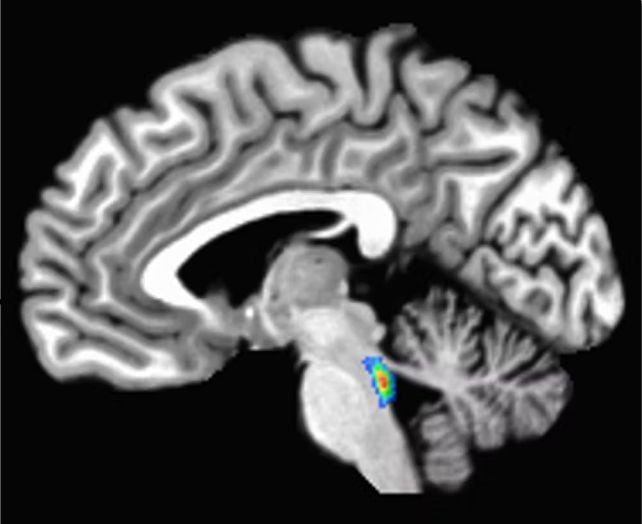

In the earliest of these changes, a tangled version of a protein called tau starts building up in a tiny region deep in the brain involved in sleep, attention, and alertness, called the locus coeruleus. Tau later spreads to the rest of the brain.

Developing tau tangles doesn't mean a person has Alzheimer's disease – in fact, it happens to nearly everyone to varying degrees. But because these changes start in the locus coeruleus, some brain researchers – myself included – see this area as a canary in the coal mine for developing Alzheimer's disease.

The locus coeruleus sits in the brain stem, the lowest part of the brain. Its name, "blue spot," comes from a pigment called neuromelanin that its cells produce.